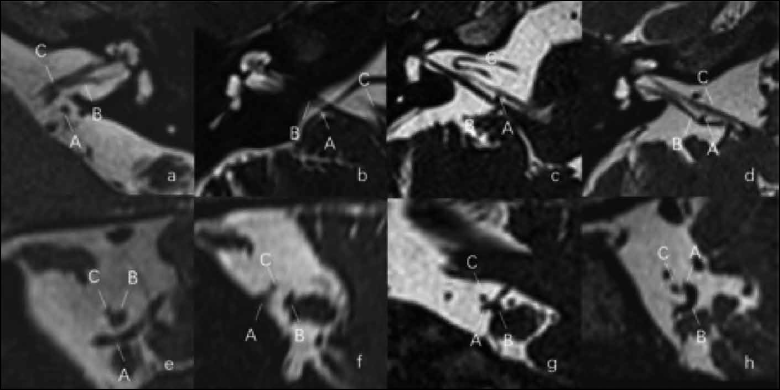

Figure 2. Chavda classification of AICA loop. (a) AICA loop (arrow) observed in CPA outside the IAC which is type I; (b) Type II in which AICA loop (arrow) is occupying no more than 50% of IAC; (c) Type III in which AICA loop (arrow) leaches more than 50% of total length of IAC.

Figure 3. Gorrie classification of AICA loop. (a,e) AICA loop (A) running separate from cranial nerve (B,C) which is type A; (b,f) Type B in which the AICA loop (A) is running adjacent to the cranial nerve (B,C); (c,g) Type C in which the AICA loop (A) runs between the 7th (C) and 8th (B) cranial nerve; (d,h) Type D in which the AICA loop (A) displacing the nerve resulting in bowing of the nerve (B).